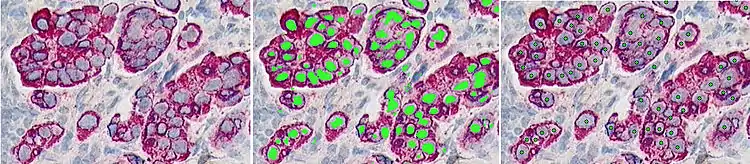

The raw microscopic image of a stained lymph node (left) from the Kohrt study,[2] a superimposed mask showing the pixel classification results (center), and finally the image is marked with the centroids of the object of interest - the cancer nuclei (right)